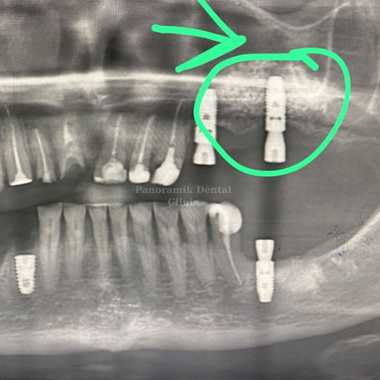

Open (lateral) sinus lifting: It is a mini-surgical operation performed with local anesthesia in cases where the bone height is below 4 millimeters.

Closed (internal) sinus lifting: It is applied in cases where the bone height is between 4mm-7mm. The floor of the sinus is raised using a special instrument called an osteotome and filled with bone graft. This procedure is performed using local anesthesia. Sinus lifting operations are painless procedures that take 30-60 minutes. İf there is enough bone tissue, implants can be installed in the same session.

Sinus lifting is a procedure performed in the dentist’s chair under local anaesthesia. The sinus area to be removed is reached by means of a small window opened through the gingiva in that area.

After the sinus membrane covering the inside of the sinus is raised to the desired level, bone powder and grafting are applied to the created space and the area is closed with sutures. Depending on the jaw structure, the stages may progress slower or faster. This situation varies from person to person.